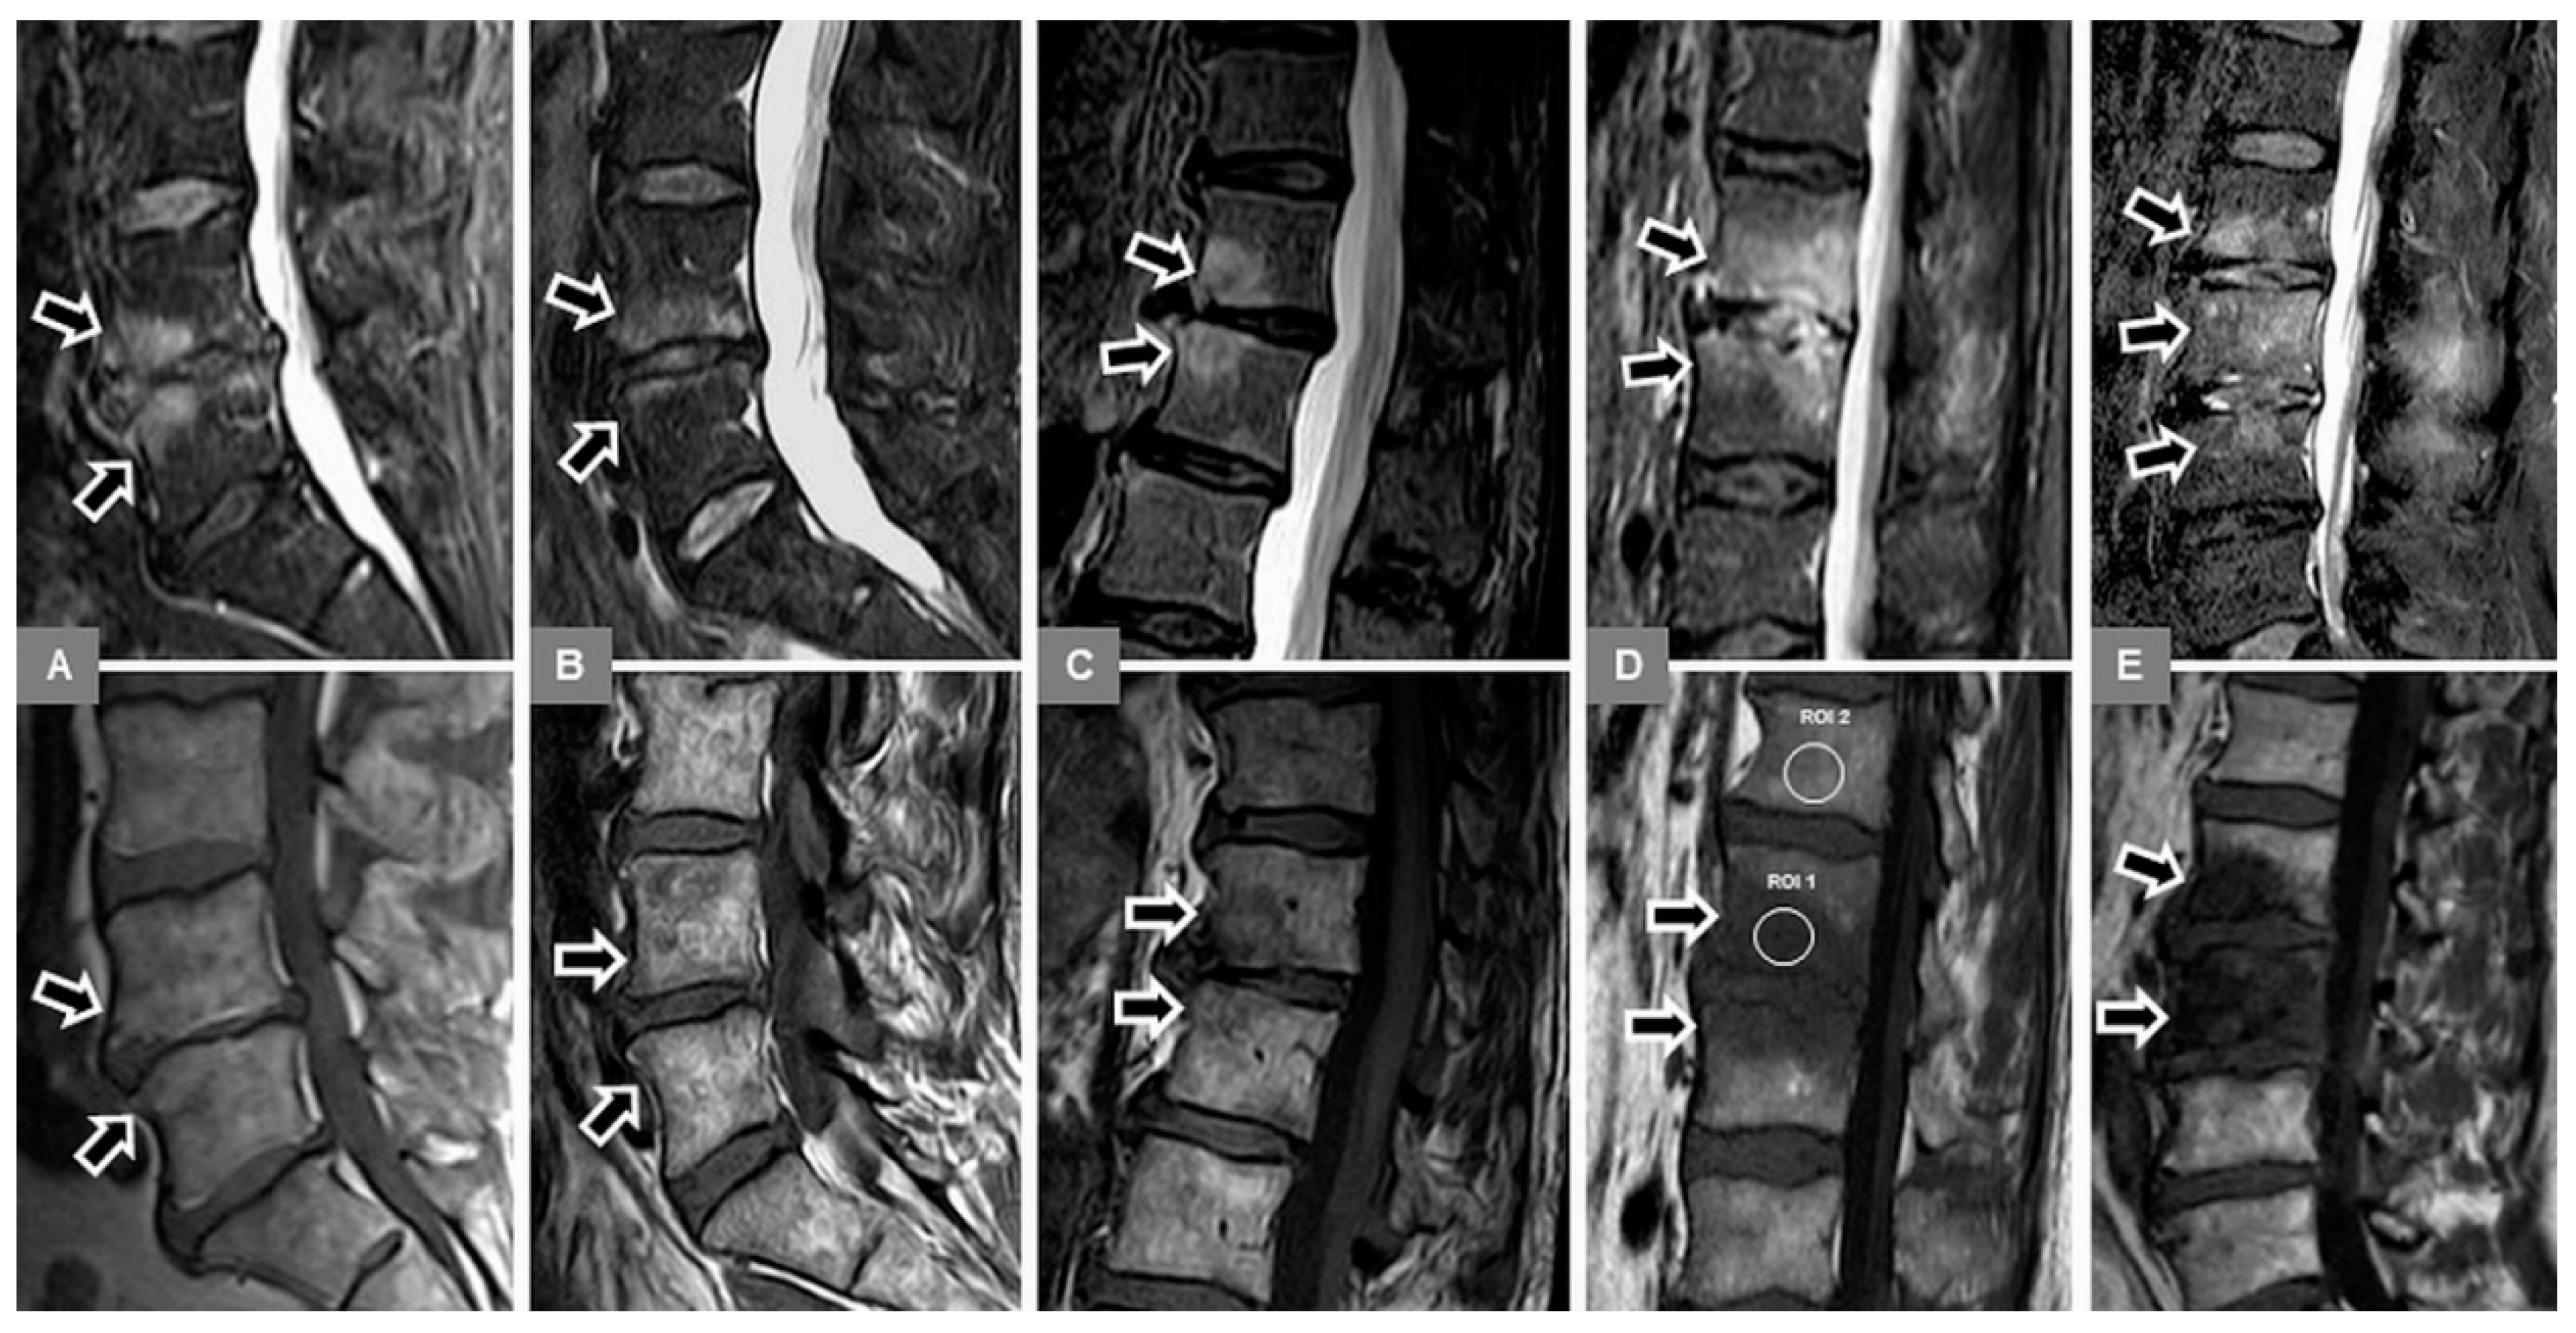

3.1. Bone Marrow Edema Extent, T1-w Signal Ratios of Edema to Unaffected Bone, and Visual T1-w Signal Assessment

3.2. Vertebral Endplate Contour

3.5. Appearance of the Intervertebral Disc

3.6. Modic Type 2 and 3 Endplate Changes